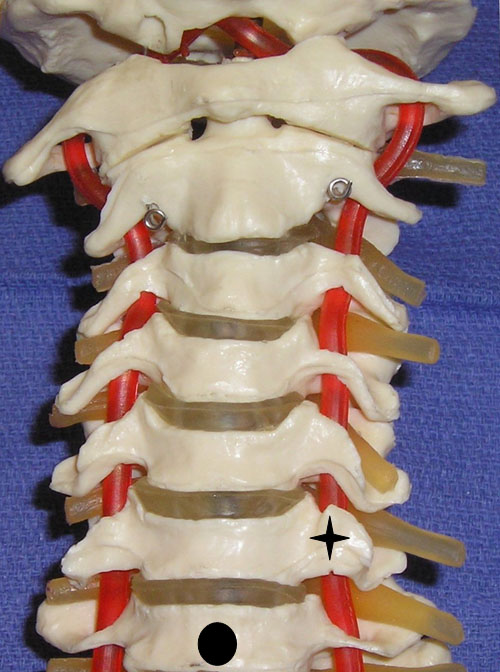

It is important to recognize the critical vascular structures in the region of the cervical spine. These critical structures include the vertebral, inferior thyroid, ascending cervical, deep cervical and radicular arteries, which often are in the vicinity of specific cervical spinal nerves as they exit their respective foramen.[14-16] The inferior thyroid artery originates from the thyrocervical trunk. The ascending cervical artery, a small branch originating from the inferior thyroid artery, may pass over the transverse processes of C6 or C7.[15] The vertebral artery, which arises from the subclavian artery, passes anteriorly at the C7 level and enters the transverse foramen in 93% of cases at the C6 level.10 In the remaining cases, the vertebral artery enters the transverse foramen at C3 (0.2%), C4 (1.0%), C5 (5%) and C7 (0.8%).[10] In cadavers, the vertebral artery average diameter was 4 mm.[14] At the C7 level the vertebral artery is unprotected by bony elements (Figure 6).

Figure 6. A cervical spine model demonstrating the large anterior tubercle of C6 (star) and the absent anterior tubercle at C7 (circle indicates body of C7).